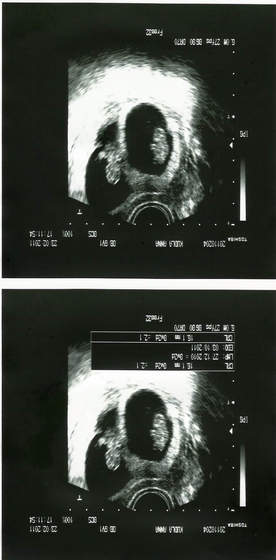

No własnie tez mi sie cos krotkawa wydaje, ale oczywiscie w gabinecie przytaknełam jak mi okreslil długosc, natomiast jak przyszlam do domu i zaczelam cos czytac to sie okazalo ze nie taka super długa. Wogole to ja jakas cichociemna jestem, nic nie wiemaga szyka trochę krótkawa ale ja się tak do końca nie znamMoja miała 4cm, wszyscy mówili że strasznie długaaa jak na bliźniaczą ciążę.

. No i wlasnie nie wiem co z tym moim ginkiem, zawsze mialam do niego zaufanie (prowadzi mi juz druga ciąze), ale teraz to sie zaczynam zastanawiac, ta szyjka krotkawa, luteine mowil zeby na razie odstawic jak z brzuch nie twardnieje.... cholera juz sama nie wiem